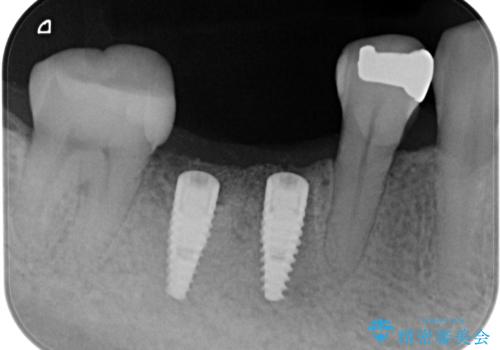

保存できない状態でしたので抜歯をして歯槽堤保存術を行いました。その後大臼歯部にインプラント治療を行いました。

欠損部に1本だけインプラントを埋入しても大きな被せ物になってしまい清掃性が悪くなるので清掃性が良くなるように2本小臼歯用のインプラントを埋入しました。

また1番奥の歯はセラミックインレーで治療を行いました。